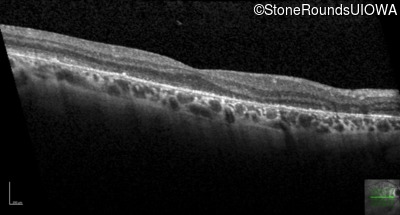

Age at visit: 56 years